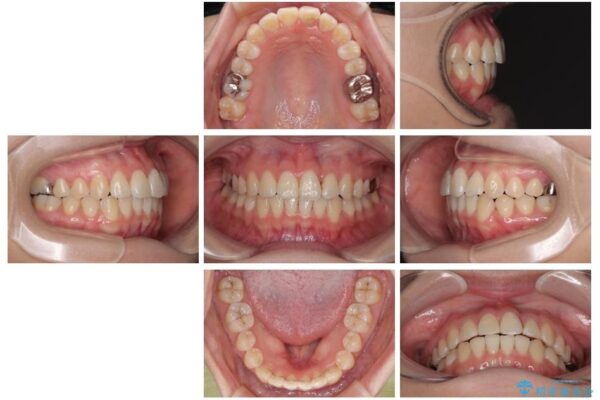

矯正治療期間はわずか10か月と、比較的短期間で終了しました。

前歯のデコボコがなくなり、見た目の印象が大きく変わっただけでなく、歯磨きがしやすくなり、むし歯や歯周病のリスクが大きく減少しました。

治療後

• 前歯のねじれ・ガタガタを10か月で改善!20代女性の矯正治療|クリアブラケットでむし歯になりにくい歯並びへ改善 治療後画像